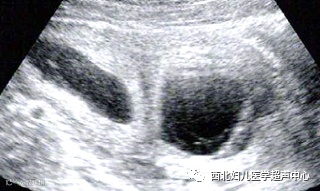

羊膜带是部分羊膜与绒毛膜分离,漂浮于羊水中形成的,是一条较为纤细的带状强回声,它的基底部是丿的形状。由于羊膜带会黏附于胎儿躯体任何部位,会对这些部位造成束缚、缠绕、压迫,使得胎儿相应部位的发育异常,这种现象被称为“羊膜束带综合征”,宫腔内羊膜带的诊断对胎儿的发育结局尤为重要。